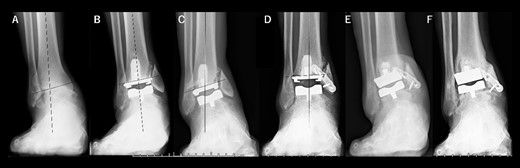

A 72-year-old man with end-stage ankle OA and severe ankle joint pain and gait dysfunction had a JSSF ankle/hindfoot scale score of 42 points. Talar tilt was 11° varus (Fig. 1A). He underwent TAA with medial malleolar osteotomy without internal fixation, and the tibial component was placed in the 5° varus position (Fig. 1B). Within 6 months, the tibial component showed varus migration, and nonunion at the medial malleolar osteotomy occurred (Fig. 1C). Revision TAA with mini-plate fixation at the medial malleolus was then performed (Fig. 1D), but the tibial component was still placed in the varus position (3° varus); subsequently, varus migration of the tibial component occurred again (Fig. 1E). After that, vitamin D administration and low intensity pulsed ultrasound treatment were continued for more than 1 year, and bone union was achieved, but both the tibial and talar components showed malposition (Fig. 1F). At present, four years after revision TAA, he can walk for more than 1.5 hours and play golf.

Radiographs of preoperative weight-bearing radiograph of the antero-posterior ankle joint in Case 1. (A) Preoperative. Talar tilt is 11° varus. Opening of the lateral gutter with os subfibulare is seen. (B) One month after surgery. Medial malleolar osteotomy without internal fixation, and tibial component placed in the 5° varus position. Opening of the lateral gutter still remains. (C) Five months after surgery. The tibial component shows varus migration, and nonunion at the medial malleolar osteotomy has occurred. Opening of the lateral gutter is exacerbated. (D) One month after revision surgery. The site of the medial malleolar osteotomy is fixed with a mini-plate, and varus positioning of the tibial component still remains (3° varus). The lateral gutter is closed. (E) Three months after revision surgery. Varus migration of the tibial component has occurred again, and bone union at the osteotomy is still not seen. (F) Four years after revision surgery. Bone union has been achieved, but both tibial and talar components show malposition. The lateral gutter is still closed.